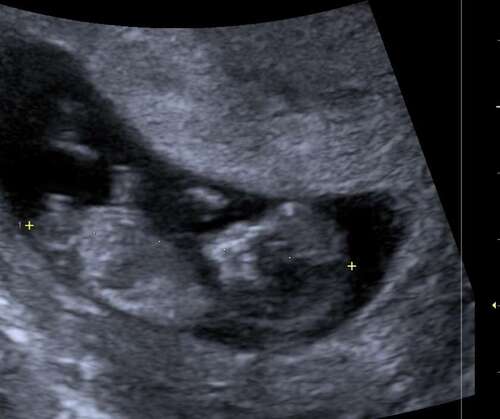

Is hier een NUB op te zien?

Helaas niets te zien. Hoeveel weken ben je hier?

10+3

Nog vroeg… maar wat denken jullie? 🤔

En op deze ook niet?

Nee sorry, niet te zien